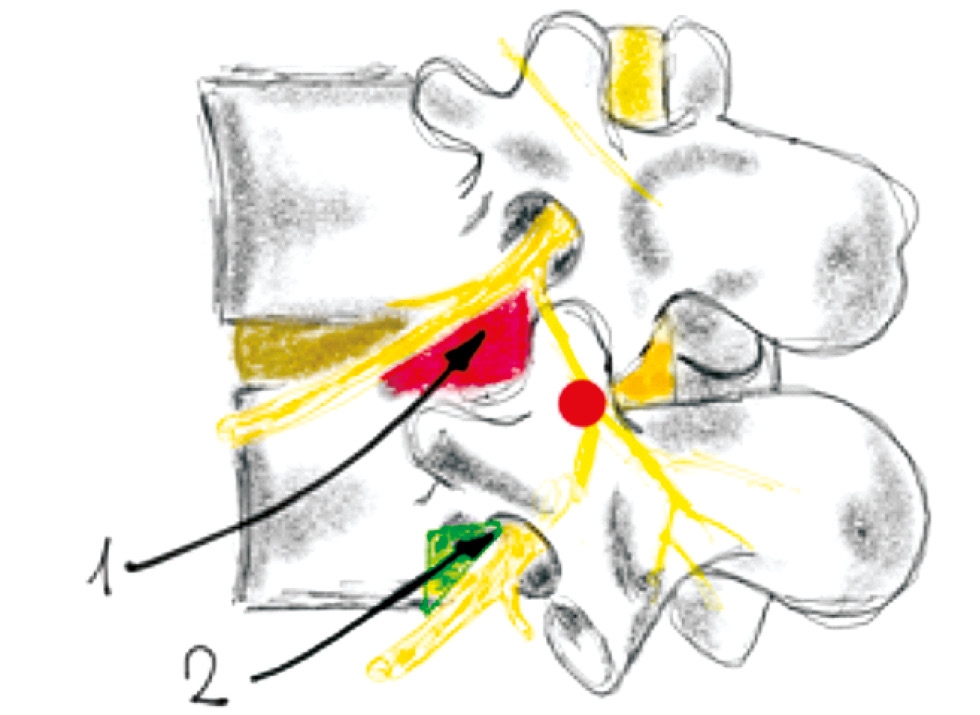

Классический метод осуществляется через безопасный треугольник (рис. 2). При боковом взгляде конечная точка должна располагаться перед межпозвонковым отверстием (кзади от тела позвонка или в субпедикулярном положении (точка, указанная цифрой 2 на рис. 2) или, наоборот, в задней части межпозвонкового отверстия (ретроневральное положение). Хотя конечное положение иглы в верхней части межпозвонкового отверстия позволяет избежать случайной травмы нервного корешка, и поэтому описывается в качестве стандартного метода в учебной литературе [6]. Существует большая вероятность встретить на пути иглы корешковую медуллярную (артерию Адамкевича) артерию в конечной точке (рис. 3) [7].

Рис. 2. Точки безопасной пункции. 1 – треугольник Камбина, 2 – cубпедикулярное введение / Fig. 2. Safe puncture points. 1 – Kambin triangle, 2 – Subpedicular

Рис. 3. Артерия Адамкевича / Fig. 3. Adamkevich artery

Для того чтобы предотвратить непреднамеренную пункцию и внутрисосудистое введение кортикостероида во время инъекции на уровне L3 и выше, используется способ через треугольник Камбина, наклонная сторона которого образована отводящим нервным путём и является основанием для нижележащего позвонка, а боковая – верхним суставным отростком, поскольку артерия Адамкевича редко пересекает эту часть отверстия [7, 8]. Этот способ также называется ретродискальным, поскольку конечная точка расположена непосредственно за диском, имеется более высокая вероятность случайного его прокола диска [9].